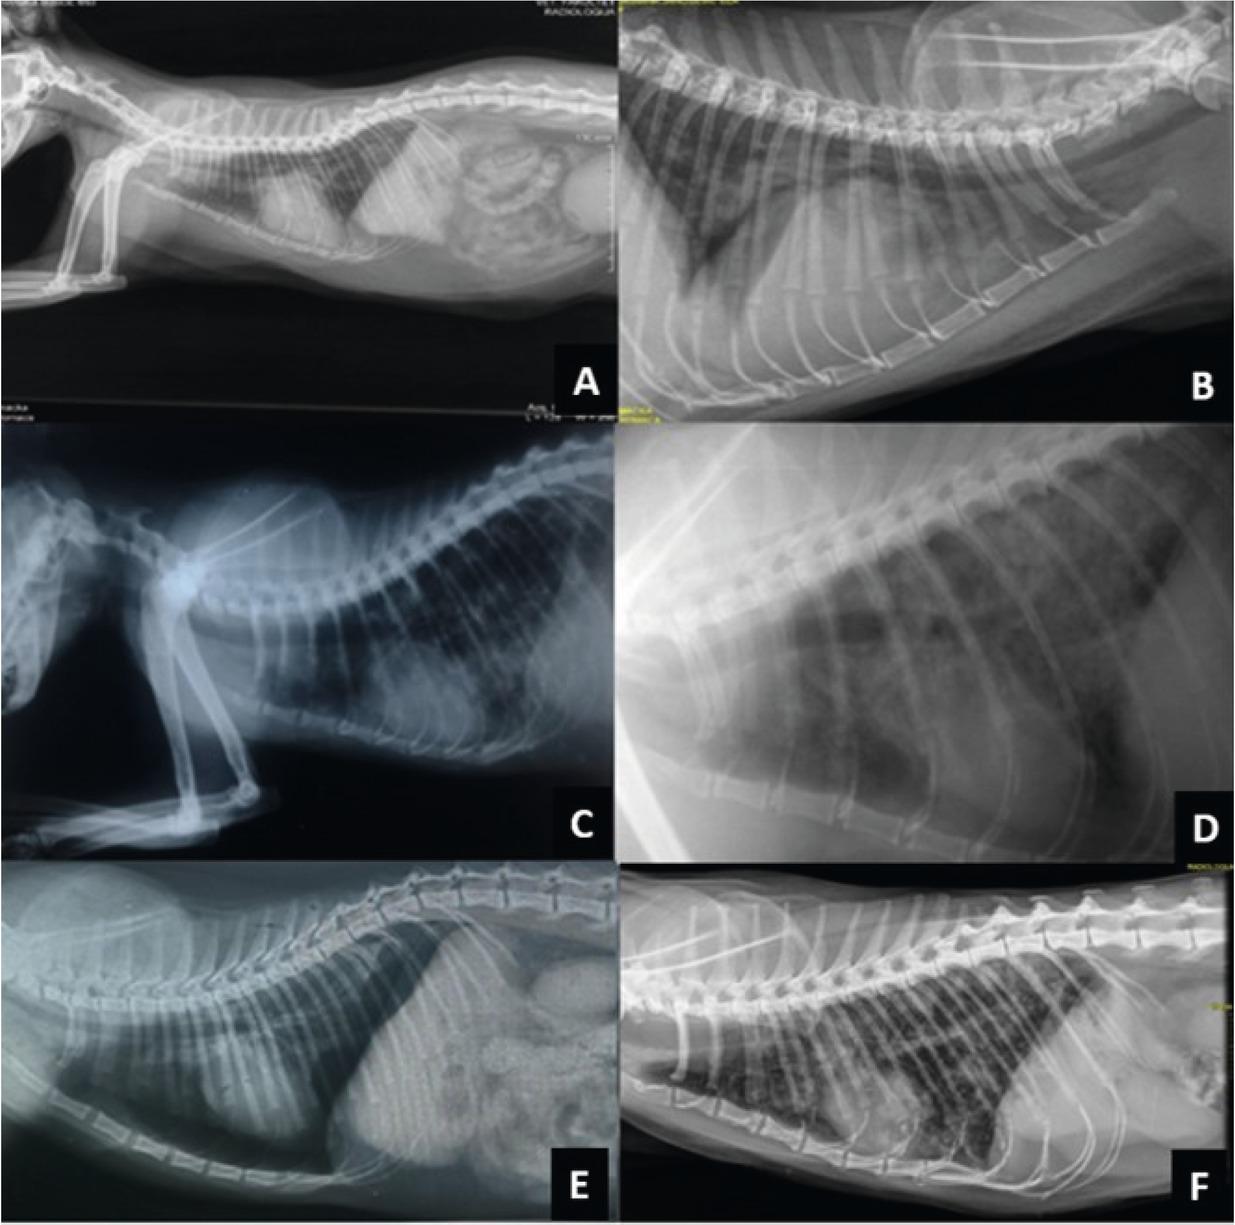

X-rays of the cats with Capillaria aerophila infection have a typical mild lung pattern across the pulmonary fields and is characterized by mild bronchial and alveolar changes and a mild reticular interstitial picture (Fig. 3) We present radiograms of the ventrodorsal and right lateral thoracic X-rays of 7 cats with C. aerophila infection. Four of them had bronchopneumonia with a mild reticular interstitial pattern or with complex lung pattern which was visible across the pulmonary fields, characterized by bronchial and alveolar changes and increased interstitial opacity due to bacterial bronchopneumonia, or viral bronchopneumonia complicated with the secondary bacterial infection, pneumothorax, edema pulmonum, bronchial wall thickening, emphysema, atelectasis, tracheal collapse, an enlargement of the pulmonary artery and pulmonary hypertension. Those changes were followed by respiratory clinical signs due to: tachypnea, dyspnea, abdominal breathing, and end-inspiratory crackles upon auscultation (Fig. 4).

(A, C, D, E, and F) right lateral thoracic and (B) left lateral thoracic X-rays of the cats with Capillaria aerophila infection.

(A) Right lateral thoracic X-ray a 9 year - old female infected with C. aerophila. A complex lung pattern is visible across the pulmonary fields, characterized by bronchial and alveolar changes and mild reticular interstitial pattern and there is an enlargement of the cardiac silhouette with collapses tracheae and ascites.

(B) Left lateral thoracic X-ray an 8,5 year - old male infected with C. aerophila. An oedema pulmonum is present and there is a large enlargement of the cardiac silhouette due to the dilated cardiomyopathy with hydropericardium present with bronchial wall thickening and increased interstitial opacity.

(C) Right lateral thoracic X-ray a 6 year - old female infected with C. aerophila. Bacterial bronchopneumonia with complex lung pattern, characterized by bronchial and alveolar changes and emphysema and atelectasis of the diaphragmatic lobes.

(D) Right lateral thoracic X-ray a 9 year - old female infected with C. aerophila. The virus caused bronchopneumonia with secondary bacterial complications and complex lung pattern, characterized by bronchial and alveolar changes with atelectasis of caudal pulmonary lobes and increased interstitial opacity.

(E) Right lateral thoracic X-ray a 7,5 year -old male infected with C. aerophila. Bacterial bronchopneumonia complicated with pneumothorax and pulmonary hypertension - there is an enlargement of the pulmonary artery of the caudal lobar pulmonary artery.

(F) Right lateral thoracic X-ray a 7,5 year -old male infected with C. aerophila. Bronchoalveolar localization of Ca with oedema pulmonum characterized by bronchial and alveolar changes and very difficult respiratory signs due to; tachypnoea, dyspnoea with abdominal breathing, and end-inspiratory crackles upon auscultation.